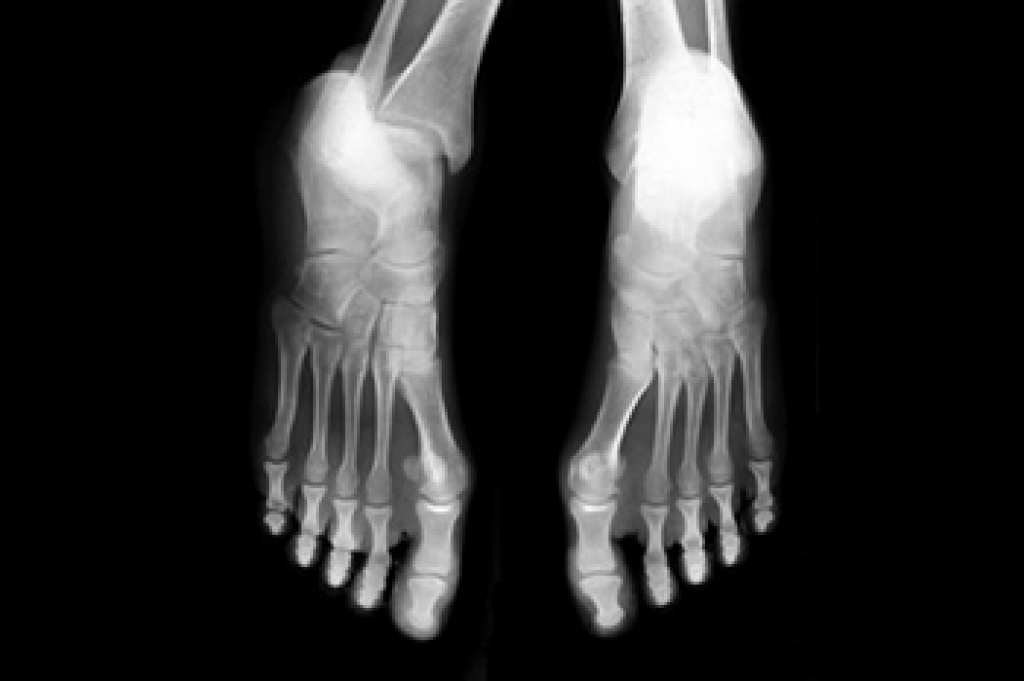

Diabetic neuropathy is nerve damage that frequently affects the feet and lower leg. It results from high blood sugar levels, causing numbness, tingling, or burning sensations in the feet, along with muscle weakness that can impact walking. Reduced sensation also makes it difficult to feel injuries, leading to unnoticed cuts or sores that heal slowly. Left untreated, these injuries may worsen, heightening the risk of infections and ulcers. For those with diabetic neuropathy, routine foot care is essential to prevent complications. A podiatrist can assist by evaluating the feet, monitoring any signs of damage, and providing guidance on footwear and skin care. This foot doctor can also suggest lifestyle modifications to support foot health and help manage the condition effectively. Regular checkups with a podiatrist help to reduce the risk of severe foot problems that are associated with diabetic neuropathy. If you have symptoms of neuropathy in the feet, it is suggested that you schedule an appointment with a podiatrist for an exam and regular treatment.

Neuropathy is a condition that leads to damage to the nerves in the body. Peripheral neuropathy, or neuropathy that affects your peripheral nervous system, usually occurs in the feet. Neuropathy can be triggered by a number of different causes. Such causes include diabetes, infections, cancers, disorders, and toxic substances.

Those with diabetes are at serious risk due to being unable to feel an ulcer on their feet. Diabetics usually also suffer from poor blood circulation. This can lead to the wound not healing, infections occurring, and the limb may have to be amputated.